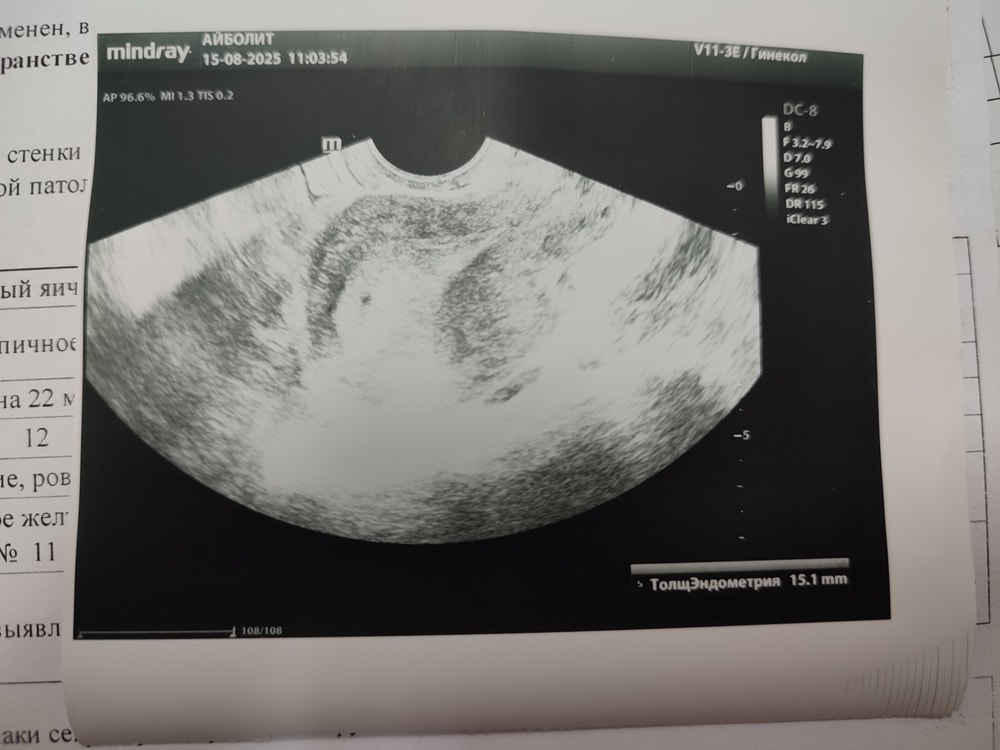

Сегодня 8й день после отмены Дюфастона и 30й ДМЦ. Пошла на УЗИ и там стало понятно на чем держится цикл. У меня была овуляция!!! При чем я даже незнаю когда, так как впервые за многое время я ее не чувствовала вообще. Что Имеем: ЖТ в правом яичнике почти 18 мм; эндометрий 15 мм пышный и ровный. Гинеколог отправила на кровь на ХГЧ.

Но я конечно в такое чудо почти не верю. Мыслю трезво, тем более с правой стороны нет трубы, да и с мужем в этот раз не старались. Придя домой стала смотреть протокол УЗИ а там на снимке какая то точка🤔похоже просто помеха. Ведь если бы был даже намёк на пя гинеколог бы сказала))